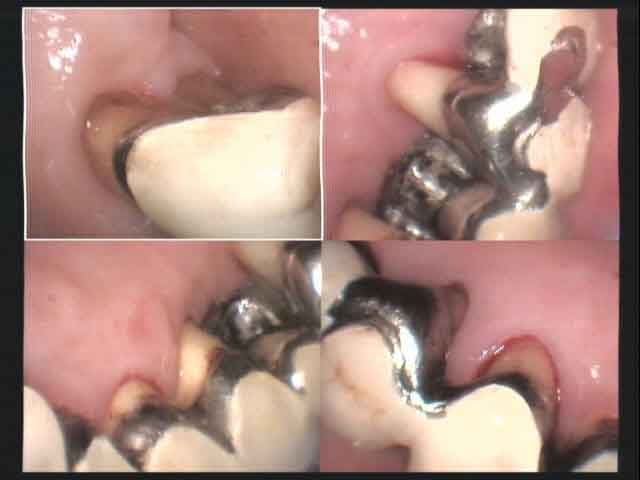

une patiente de 57 ans, que je traîne depuis 15 ans, je n'ai pas posé les bridges...

impossible de lui faire admettre que le bazar va se casser la figure, elle dit "un problème à la fois..."

tout est stable, elle n'éprouve pas de douleur, nettoie assez moyennement, sait qu'un jour elle va devoir porter une autre prothèse, s'imagine que les implants sont une panacée universelle, n'admet pas que je lui tienne un discours alarmiste, etc...

que dois-je faire ? laisser les paropathogènes s'amuser pour que le bazar se casse plus vite la gueule, ou tenter de maintenir le navire à flots coûte que coûte ?

la dame très sympathique n'a jamais discuté les honoraires demandés alors que je cherche à éteindre le feu sans jamais réussir à l'éteindre...

j'ai beau lui dire qu'étant donné les difficultés d'accès au nettoyage, etc... le cas est condamné, rien n'y fait...

Alhoun, que fais-tu dans ce cas là ? et pourtant nous sommes en train de perde de l'os au maxillaire !!!!!!!!!!!!! je le sais pertinemment..

En bas les choses sont moins dramatiques, il y a de quoi faire, mais en haut !!!???

pour revenir à tes images:

1-depuis le temps: achète un scanner.

2- on ne voit pas grand chose, mais on voit tout de même des alvéolyses terminales sur les dents distales: extraie ces dents bordel, et si elle n'a pas de sous, fais lui un stellite. ce seront là deux foyers infectieux en moins.